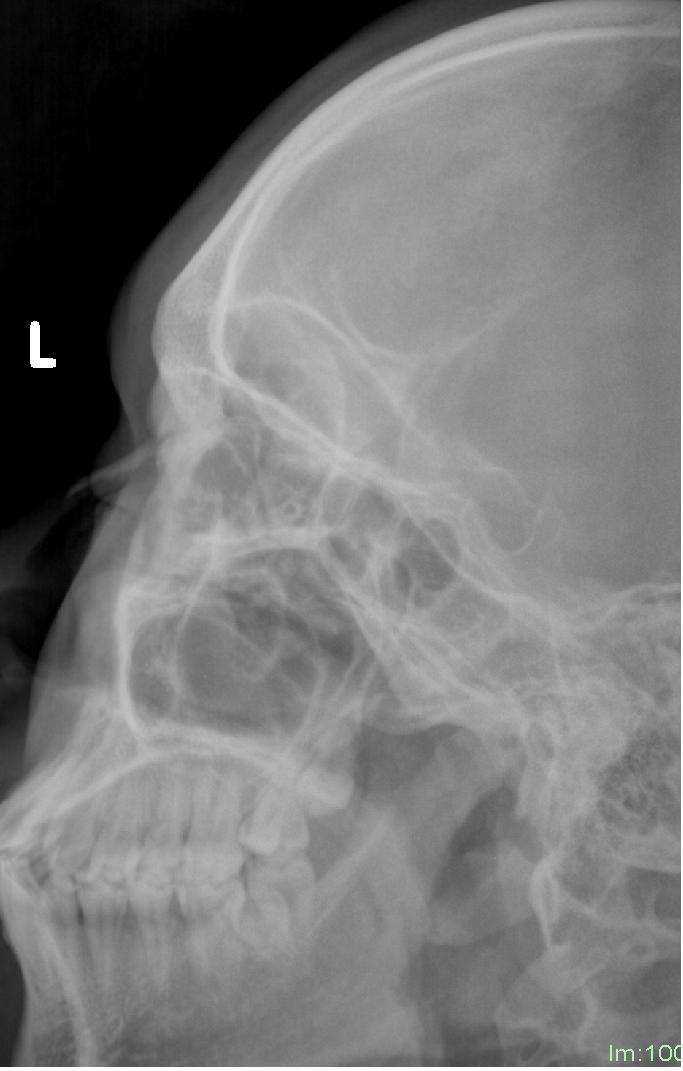

鼻部骨折 X射線檢查

鼻骨骨折是拍x线平片还是ct呢 鼻骨骨折 鼻骨骨折检查